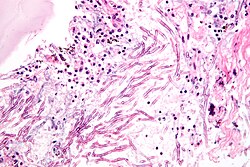

Mucormycosis

General

- Causative organism: Mucorales.

- Kingdom: Fungi.

- AKA Zygomycota (zygomycosis).

- Associated with diabetes, immunodeficiency.

Microscopic

Features:[5]

- Branching hyphae with variable width.

- Granulomata associated.

Notes:

- Not septated.

- Branching angle typically ~90 degrees.

Images

- Zygomycosis.jpg

Zygomycosis - cytology. (WC)